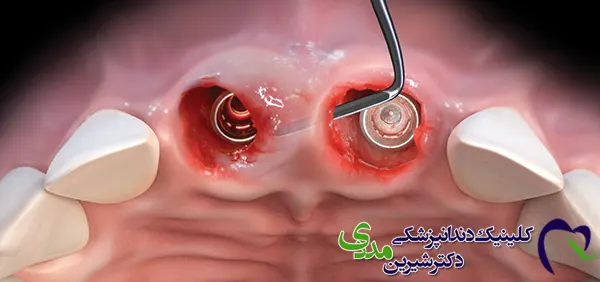

ایمپلنت پانچ، که به آن ایمپلنت فوری، ایمپلنت بدون درد و خونریزی یا ایمپلنت فلپ لس هم میگویند، روشی نوین برای جایگزینی دندانهای از دست رفته است. این روش در مقایسه با روش سنتی ایمپلنت، که نیاز به جراحی و برش لثه دارد، مزایای بیشتری دارد. در این روش، لثه به طور کامل کنار زده نمیشود و فقط با استفاده از ابزارهای ظریف، سوراخی کوچک در لثه ایجاد شده و ایمپلنت مستقیماً در استخوان فک قرار داده میشود.

ایجاد سوراخ: با استفاده از ابزارهای ظریف، سوراخی کوچک در لثه ایجاد میشود.

قرار دادن ایمپلنت: ایمپلنت به طور مستقیم در استخوان فک قرار داده میشود.

قرار دادن روکش موقت: در برخی موارد، در همان جلسه روکش موقت روی ایمپلنت قرار داده میشود.